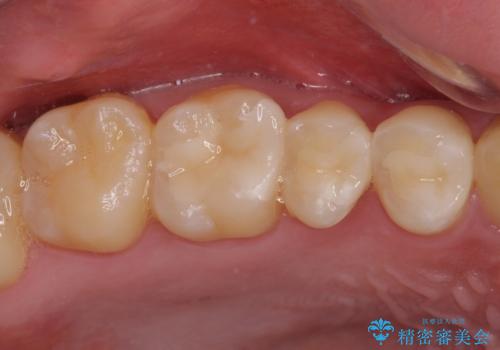

銀歯を白くしたい セラミックによる審美歯科治療

途中来院されない時期があったため、初診から終了まで期間がかかりましたが、根管治療を行った歯の根尖病変はいずれも改善を確認することができました。

口腔内の金属が全てなくなり、患者様には大変満足していただきました。